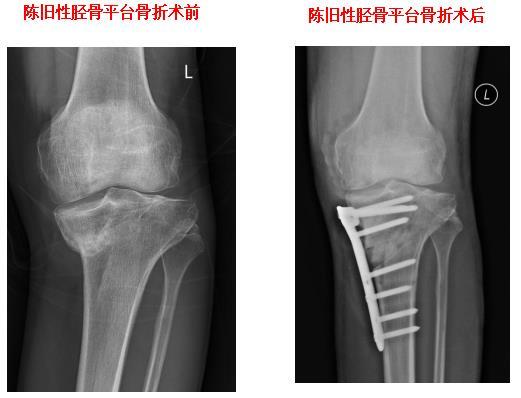

HTO截骨矫正膝关节内翻畸形

胫骨平台粉碎性骨折

膝关节单髁置换